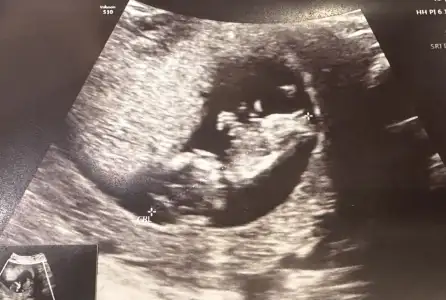

Nub teorisine göre cinsiyet tahmini yapabilen var mııı

Bizde 13 haftalık olduk bana da tahminde bulunabilir misiniz çok merak ediyorum 💕💕